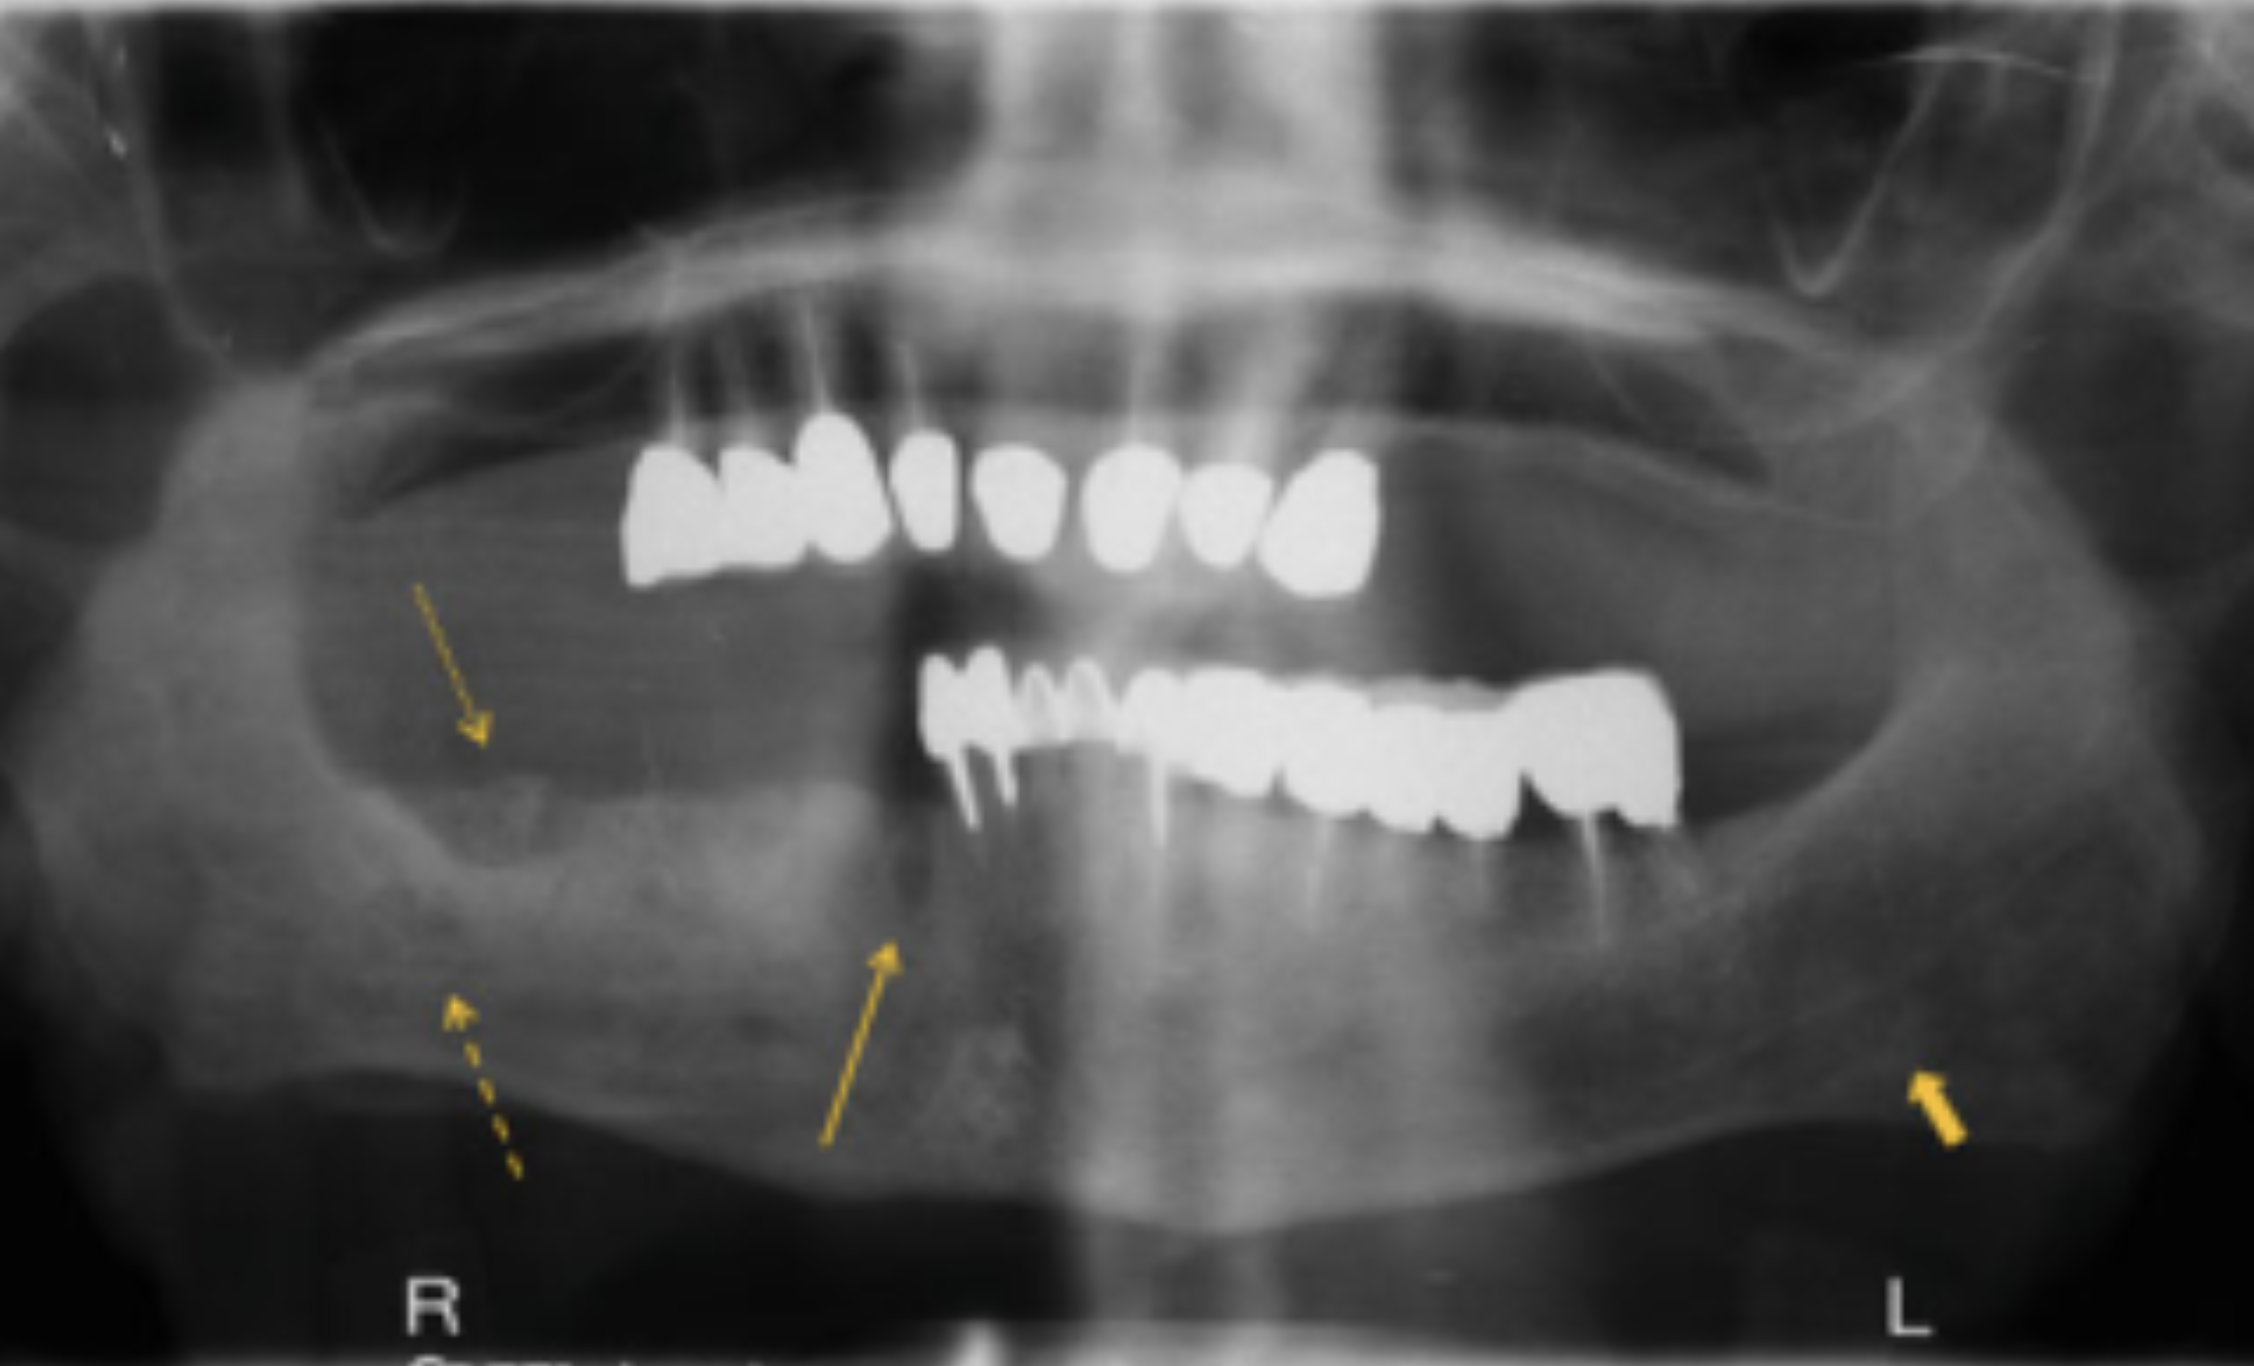

Các tổn thương xuất hiện dưới dạng các vùng xương hoại tử lộ ra màu vàng hoặc trắng có chiều dài từ vài milimet đến vài centimet (Hình 1). Bề mặt có thể gồ ghề, gây kích ứng lưỡi và đôi khi loét do chấn thương (Hình 2 ). Các mô mềm xung quanh thường đỏ và sưng lên để đáp ứng với sự nhiễm khuẩn nặng ở mô xương chết (Hình 3), hoặc hàm dưới có thể trở nên "giòn" hơn và có nguy cơ gãy xương. Dù các nghiên cứu cho thấy việc chụp X quang là không cần thiết cho chẩn đoán, nhưng nếu đáp ứng điều trị ban đầu chưa tốt hoặc nghi ngờ có biến chứng (Hình 4) thì nên chụp X quang toàn hàm hoặc CT Scan.

| XÉT NGHIỆM CHẨN ĐOÁN | Không có; xem xét chụp X quang toàn hàm hoặc CT Scan nếu có gãy xương hoặc nghi ngờ có khối xương hoại tử lớn. |